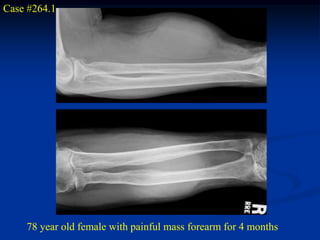

Case #264.1

78 year old female with painful mass forearm for 4 months

Case #264.1 78 year old female with painful mass forearm for 4 months